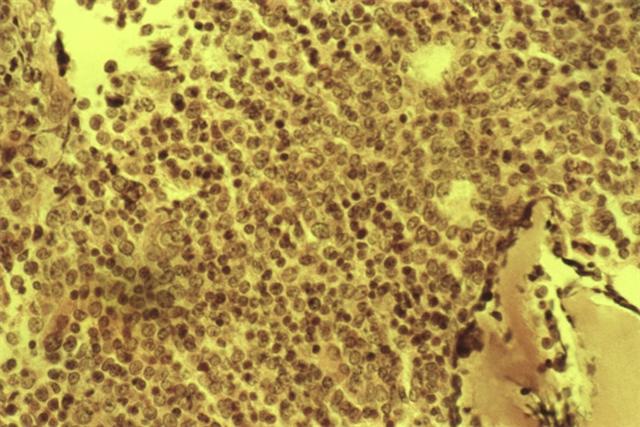

Рис. 2. Микропрепарат костного мозга при остром миелобластном лейкозе: диффузная лейкозная инфильтрация. Окраска гематоксилином и эозином; ´400.